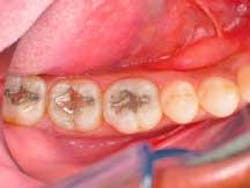

A male patient presented with failing 15-year-old amalgam restorations on Teeth Nos. 17 through 19 (Figure 1) and cold sensitivity on Tooth No. 19. Teeth Nos. 17 and 18 required Class I restorations, while Tooth No. 19 required a Class II restoration. Direct composite resin restorations (4 Seasons Universal Composite and 4 Seasons Flow) were deemed the more appropriate treatment for this patient. This was confirmed following removal of the amalgam restorations, which showed the shallowness of the cavities.